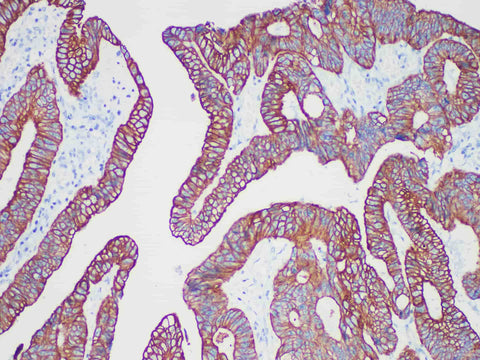

CAM5.2 Monoclonal Antibody

Applications IHC-P

Tissue Specificity Colon cancer

CAM5.2 is a commonly used very low molecular weight keratin. In normal tissues, the secretory epithelium (glandular epithelium) is positive for CAM5.2, but the stratified squamous epithelium is negative. It is one of the commonly used markers in glandular epithelium and various adenocarcinomas. CAM5.2 can be used in combination with high molecular weight keratin to distinguish adenocarcinoma from squamous cell carcinoma. In addition, CAM5.2 is generally considered to be suitable for the detection of metastatic breast cancer in (sentinel) lymph nodes.